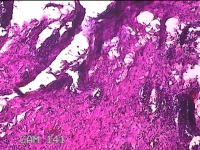

性别

男

年龄

51岁

临床诊断

躯干皮脂腺囊肿

一般病史

发现腰背部结节20余年,伴近日局部隐痛不适及少许渗出。

标本名称

腰背部结节

大体所见

灰白暗红色结节1.8x0.5x0.3cm一个,表面糜烂,切面灰白暗红色,质软。

图1